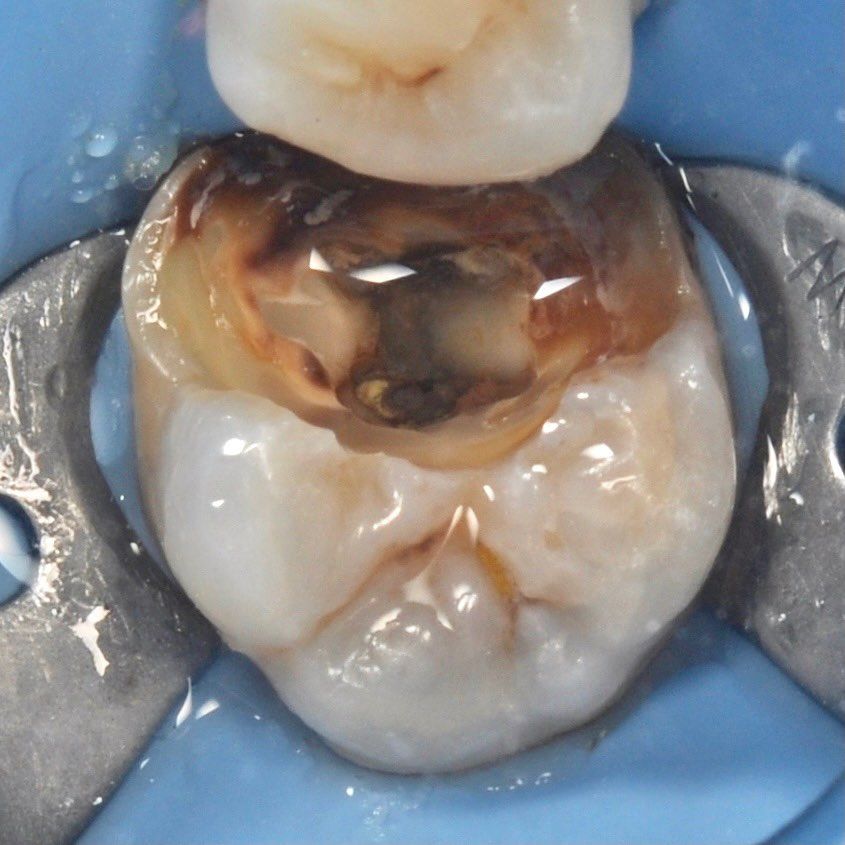

тщательная обработка каналов

Точное определение геометрии каналов и их качественная обработка

Каналы наших зубов можно представить как дерево имеющее множество ответвлений. Задача врача провести их обработку сохранив ткани зуба.